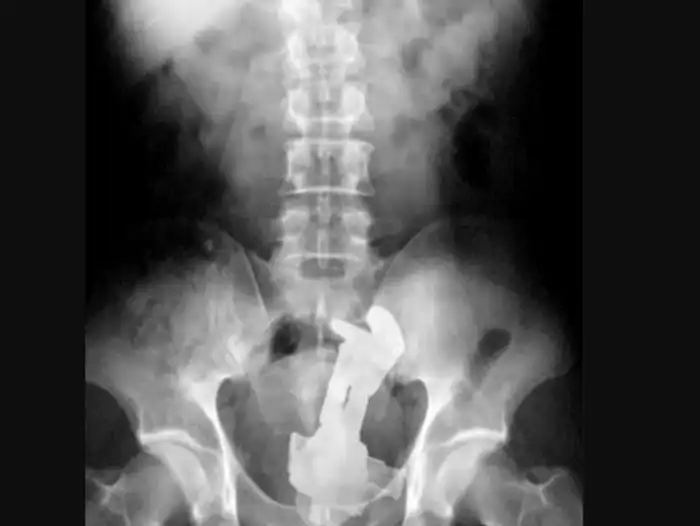

52-летняя Маргарет Даалман просто захотела поесть серебра, поэтому навернула 78 ложек и вилок.